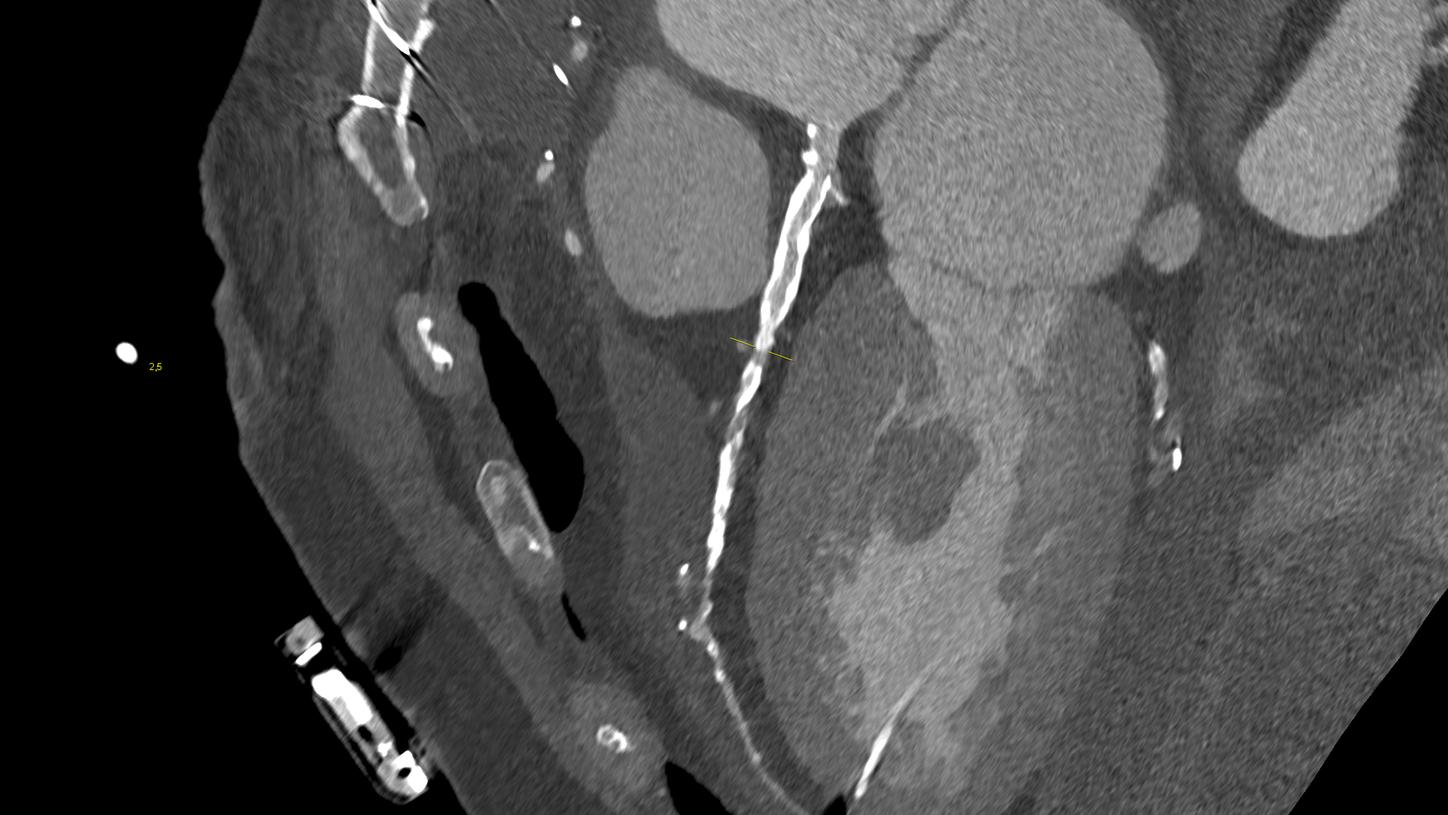

At the heart of NAEOTOM Alpha® is a radically new photon-counting detector. The QuantaMax detector directly converts X-rays into an electrical signal, which is then used to create an image. The energy of each X-ray is measured, so spectral information is available for every scan, and the images are contrast-rich with high spatial resolution at the same dose. Combining the high spatial resolution of the QuantaMax photon-counting detector with our Dual Source temporal resolution enables the visualization of fine details for increased diagnostic confidence.

QuantaMax, the first photon-counting detector, overcomes the limitations of conventional CT detectors by providing data at high spatial resolution, without electronic noise and with improved contrast-to-noise ratio.

Vectron X-ray tube enables high image quality, even for patients with high BMI. The microfocal spot (0.4 mm x 0.5 mm) allows to utilize the high spatial resolution of the QuantaMax detectors.